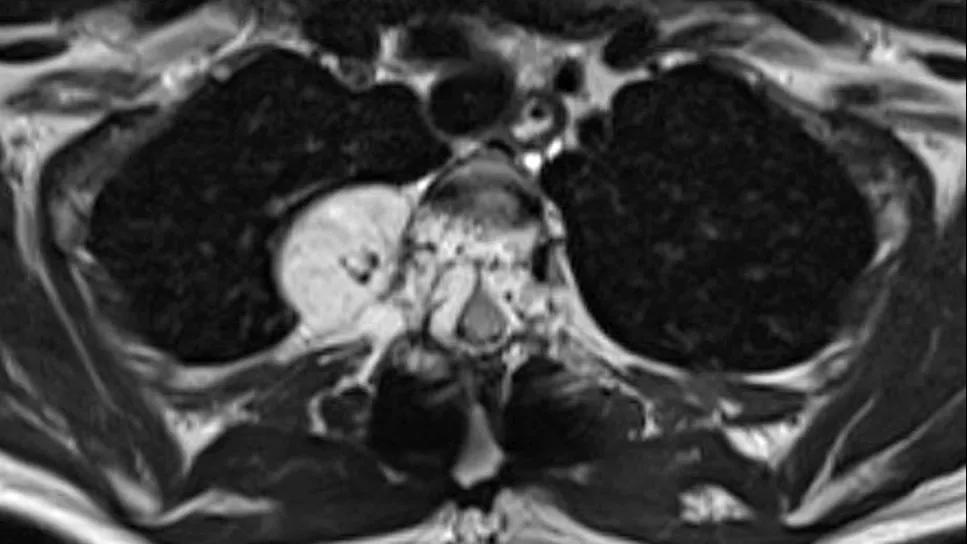

vertebral hemangioma on MRI

Spine stereotactic radiosurgery (sSRS) appears to be a safe and effective noninvasive treatment for patients with symptomatic vertebral hemangiomas with epidural extension (SVHEE), whether used as monotherapy or after surgical decompression. So concludes a retrospective review of patients with the rare condition published by Cleveland Clinic researchers in Neurosurgery (Epub 2024 Apr 19).